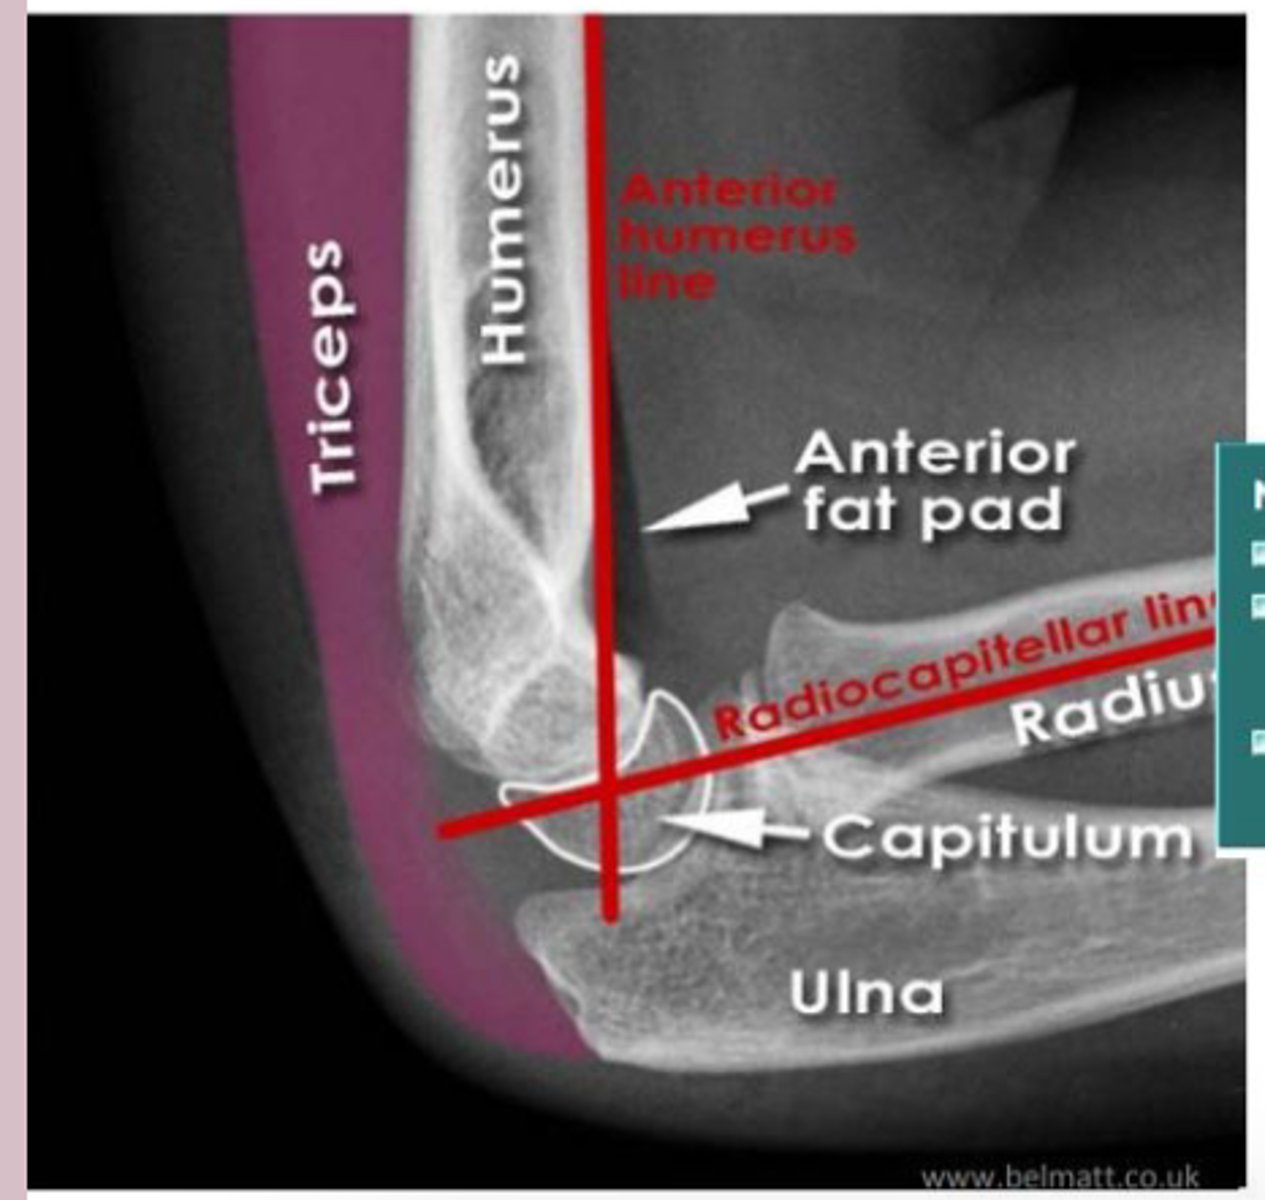

elbow

knowt flashcard image

elbow lateral